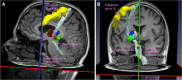

The thalamus is an essential relay station in the cortical-subcortical connections. It is characterized by a complex anatomical architecture composed of numerous small nuclei, which mediate the involvement of the thalamus in a wide range of neurological functions. We present a novel framework for segmenting the thalamic nuclei, which explores the orientation distribution functions (ODFs) from diffusion magnetic resonance images at 3 T. The differentiation of the complex intra-thalamic microstructure is improved by using the spherical harmonic (SH) representation of the ODFs, which provides full angular characterization of the diffusion process in each voxel. The clustering was performed using the k-means algorithm initialized in a data-driven manner. The method was tested on 35 healthy volunteers and our results show a robust, reproducible and accurate segmentation of the thalamus in seven nuclei groups. Six of them closely matched the anatomy and were labeled as anterior, ventral anterior, medio-dorsal, ventral latero-ventral, ventral latero-dorsal and pulvinar, while the seventh cluster included the centro-lateral and the latero-posterior nuclei. Results were evaluated both qualitatively, by comparing the segmented nuclei to the histological atlas of Morel, and quantitatively, by measuring the clusters' extent and the clusters' spatial distribution across subjects and hemispheres. We also showed the robustness of our approach across different sequences and scanners, as well as intra-subject reproducibility of the segmented clusters using additional two scan-rescan datasets. We also observed an overlap between the path of the main long-connection tracts passing through the thalamus and the spatial distribution of the nuclei identified with our clustering algorithm. Our approach, based on SH representations of the ODFs, outperforms the one based on angular differences between the principle diffusion directions, which is considered so far as state-of-the-art method. Our findings show an anatomically reliable segmentation of the main groups of thalamic nuclei that could be of potential use in many clinical applications.